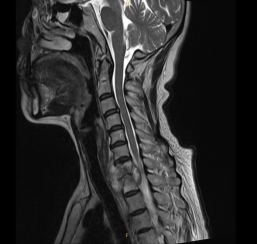

该女性患者,以“右侧肩背部疼痛双上肢麻木半年” 伴吞咽困难主诉入院。入院MRI检查可见“颈7胸1椎体骨质破坏,椎管受压”。科主任陈其亮主任医师组织科室讨论并仔细查看病人后认为:病变位于活动灵活前凸的颈椎和相对固定后凸的胸椎的交界处,更易导致后凸畸形或局部不稳定,其椎管相对较小,椎管壁与硬脊膜囊前方间隙较窄,椎管内脊髓缓冲空间小,当结核病灶侵及硬膜外、压迫硬膜囊时,容易导致截瘫。由于患者已经出现明显神经受压症状,为避免出现截瘫等严重并发症应行手术解除压迫,由于颈胸段椎体部位深,前路手术前方有胸骨、胸锁关节阻挡,病变椎体周围有众多大血管、喉返神经、胸导管和交感神经,显露均较为困难,综合病变特征认为虽然前路手术风险大,但可以彻底清除病灶,椎管减压效果更好,权衡利弊后经术前充分准备于近日在手麻科插管全麻配合下成功经低位颈前入路实施病灶清除、椎管减压及植骨内固定术,术后次日查房患者神经压迫症状明显缓解。